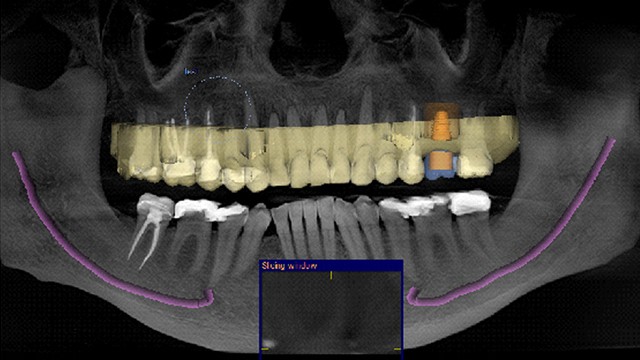

57 y.o male presents to Parker Family Dental for implant placement for missing tooth upper left. 3D Dental CT scan is taken and implant surgery is performed digitally. The patient’s digital impression is merged with the CT scan to create a digital crown for the missing tooth upper left.

The digital implant is checked in three dimensions to determine proper functionality with the crown and avoidance of the patient’s maxillary sinus.